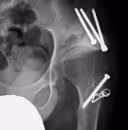

①高位脱臼性股関節症

脱臼している股関節を原臼位(元の位置)に再建するために大腿骨の短縮骨きりを同時に行い人工股関節を設置します。